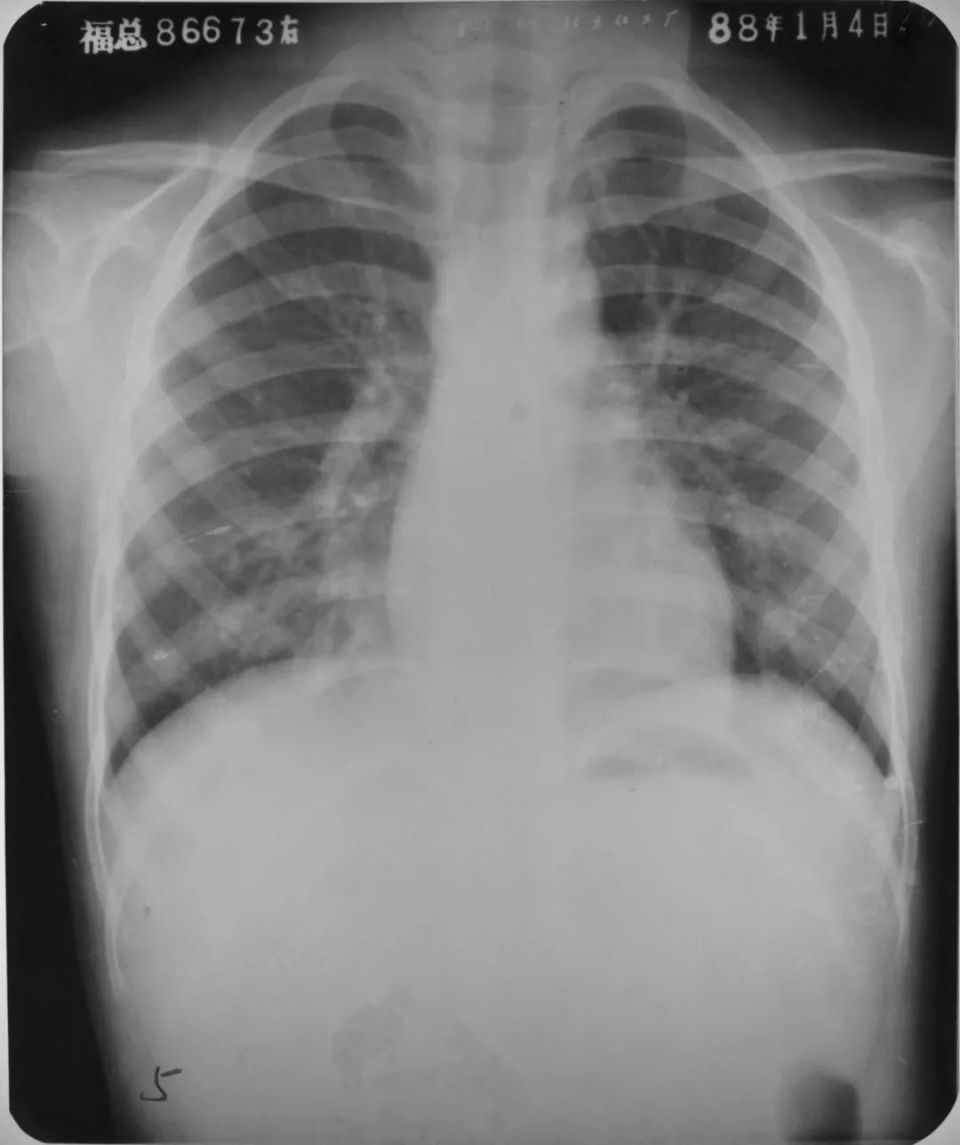

右肺下叶后基底段大叶性炎症

图片

胸部正侧位片:右肺下叶见片状致密影,右侧膈面及邻近胸廓边缘模糊(箭头所示),心缘清楚